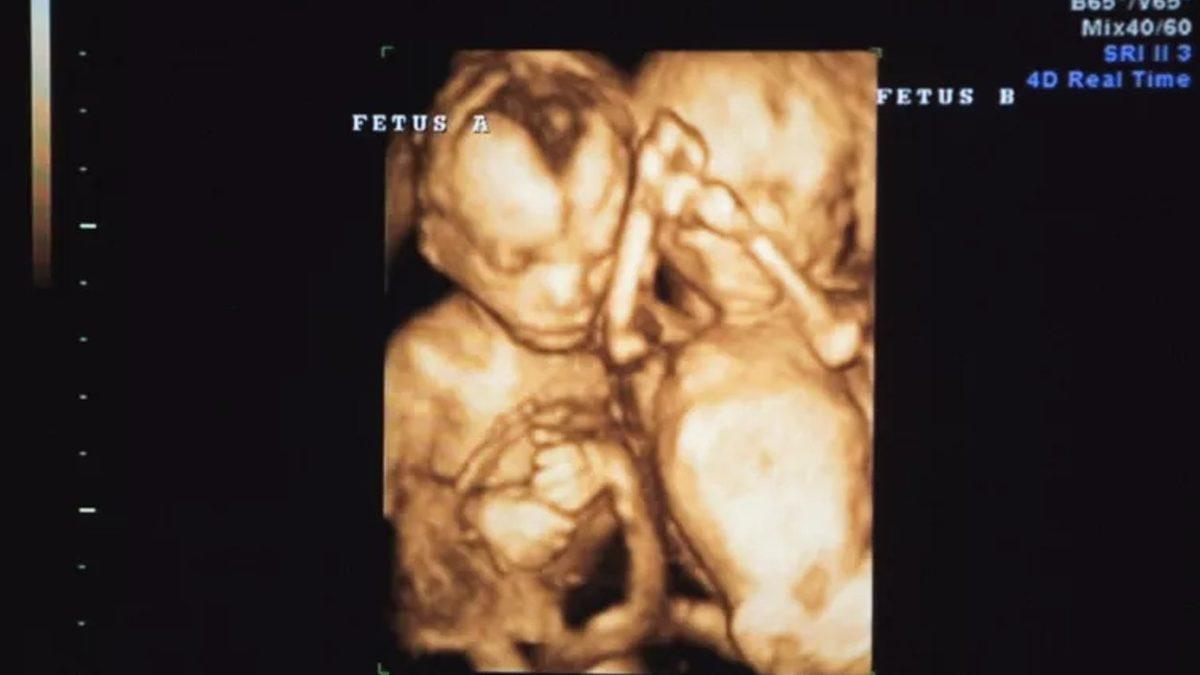

Döllenme sırasında embriyoyu oluşturan hücre kümeleri normal bir biçimde geliştiğinde sağlıklı ikizler meydana gelirken, iki embriyo farklı boyutlardaysa, büyük olan yeterli miktarda plasenta kanını alıyor ve gelişmeye devam ederek normal bir fetüs halini alıyor. Küçük olan ise elverişsiz rahim içi koşullar nedeniyle gelişemeyerek hayatını kaybediyor ve o bölgede cansız bir şekilde kalıyor.

Bir görüşe göre fetüsün kalbi, beyni, gözbebekleri, bağırsakları ya da farklı uzuvları içeren organları farklılaşırken, bir diğer durumda normal ikizler, simetrik yapışık ikizler olarak deforme olurlar.

Gebelikler ortalama 38-40 hafta sürerken, bir annenin gebeliğinin 25. haftasında bir kitle tespit edildi ve bu kitleler hamilelik ilerledikçe artış gösterdi. Ultrason ve MR ile tespit edilen bu kitleler incelendiğinde, oluşumların fetüs içinde fetüs vakasıyla sonuçlanacağı anlaşıldı.